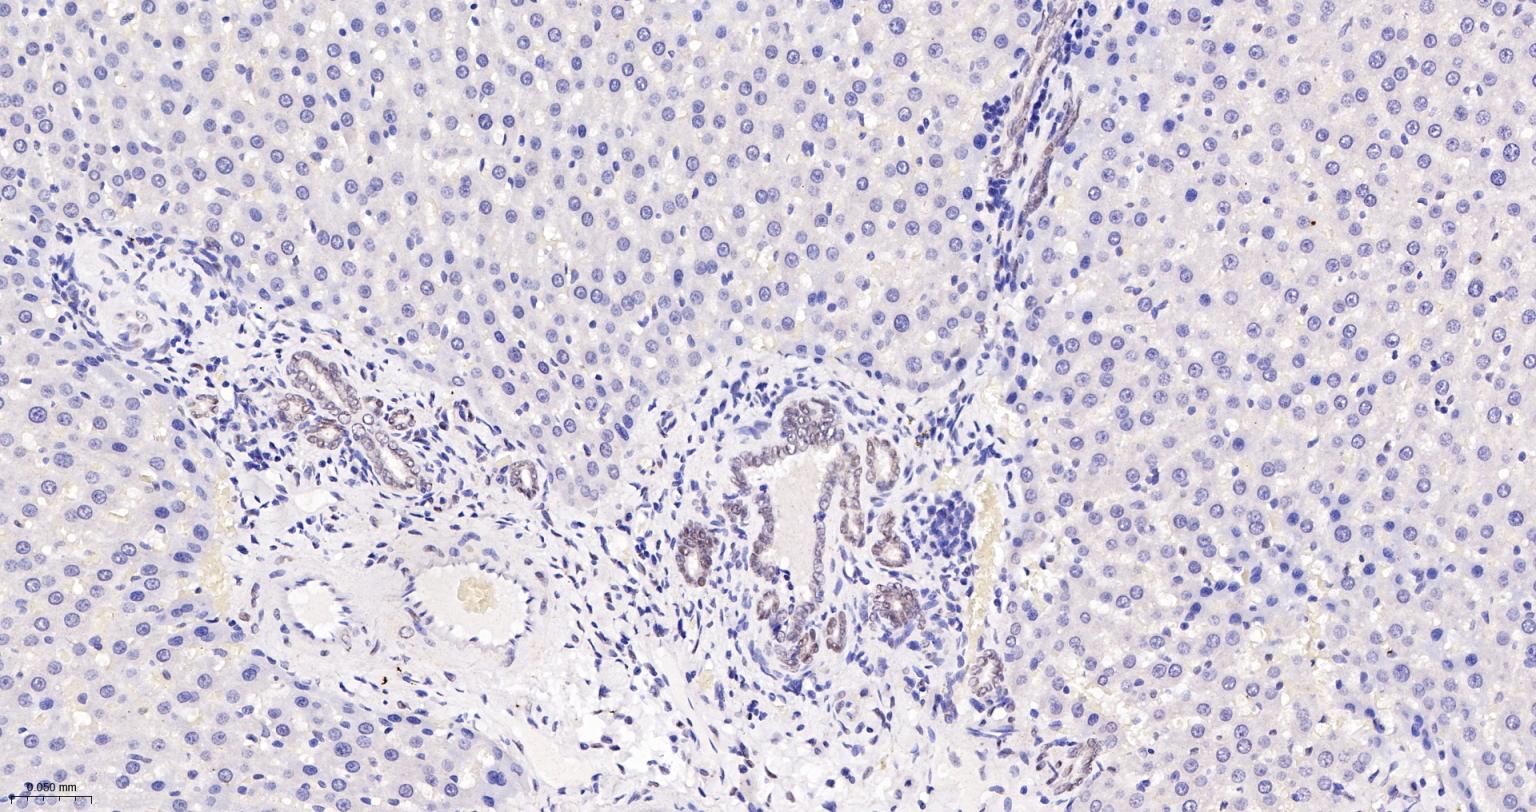

Paraformaldehyde-fixed, paraffin embedded Human Endometrial; Antigen retrieval by boiling in sodium citrate buffer (pH6.0) for 15 min; The section was incubated with TEAD1 Monoclonal Antibody, Unconjugated (bsm-63274R) at 1:200 overnight at 4°C, followed by conjugation to the bs-0295G-HRP and DAB (C-0010) staining.